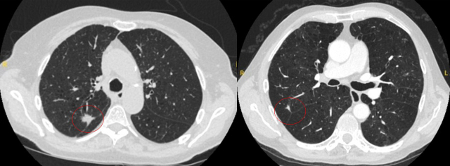

Computed tomography (CT) sections from two cases with benign perifissural nodules. Note the smooth margins and the normal undisturbed adjacent fissure

From the collection of Dr George Tsaknis, MD, PhD, FRCP(London), MRQA, MAcadMEd, PGCert; used with permission